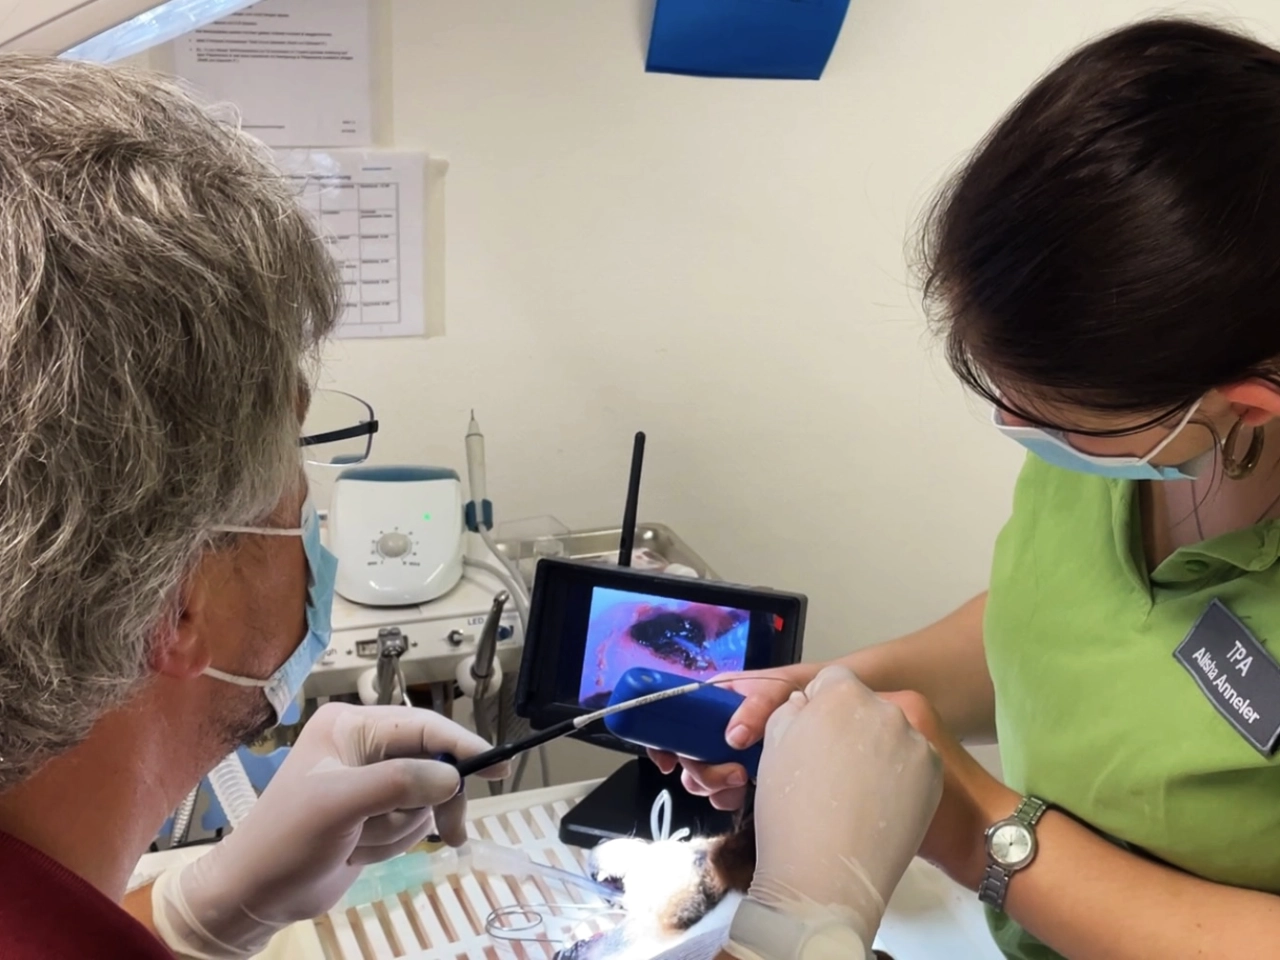

Zahnmedizin

Gesunde Zähne bedeuten Lebensfreude – wir kümmern uns um die Zahngesundheit Ihres Tieres.